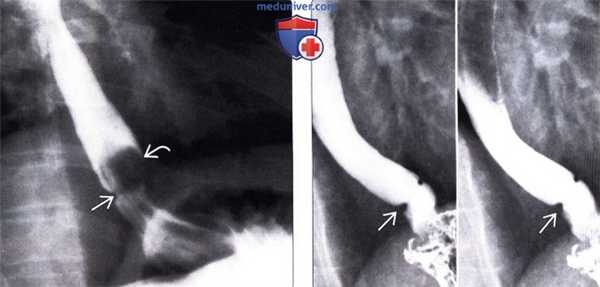

(Слева) При рентгеноскопии подростка, предъявляющего жалобы на острую боль в грудной клетке, возникшую после проглатывания куска мяса, определяется кольцо Шацкого, виден дефект наполнения, обусловленный искомым кусочком мяса, находящимся над кольцом.

(Справа) Изначально на рентгенограммах (не представлены), не было обнаружено патологических изменений. И только на последующих рентгенограммах, полученных при задержке дыхания на глубоком вдохе, с использованием маневра Вальсальвы, было выявлено кольцо Шацкого В в области пищеводно-желудочного перехода. Кольцо Шацкого может быть пропущено, если оно находится не под прямым углом по отношению к пучку рентгеновских лучей, или, если пищевод недостаточно туго заполнен контрастом.

(Справа) На рентгенограмме, полученной во время рентгеноскопии пищевода со взвесью сульфата бария, визуализируется грыжа пищеводного отверстия циафрагмы В небольшого размера и кольцо Шацкого, приводящее к сужению просвета пищевода до 5-7 мм. Симптоматическое сужение просвета за счет кольца Шацкого (в области кольца В), скорее всего, является результатом рефлюкс-эзофагита. (Слева) При рентгеноскопии подростка, предъявляющего жалобы на острую боль в грудной клетке, возникшую после проглатывания куска мяса, определяется кольцо Шацкого, виден дефект наполнения, обусловленный искомым кусочком мяса, находящимся над кольцом.